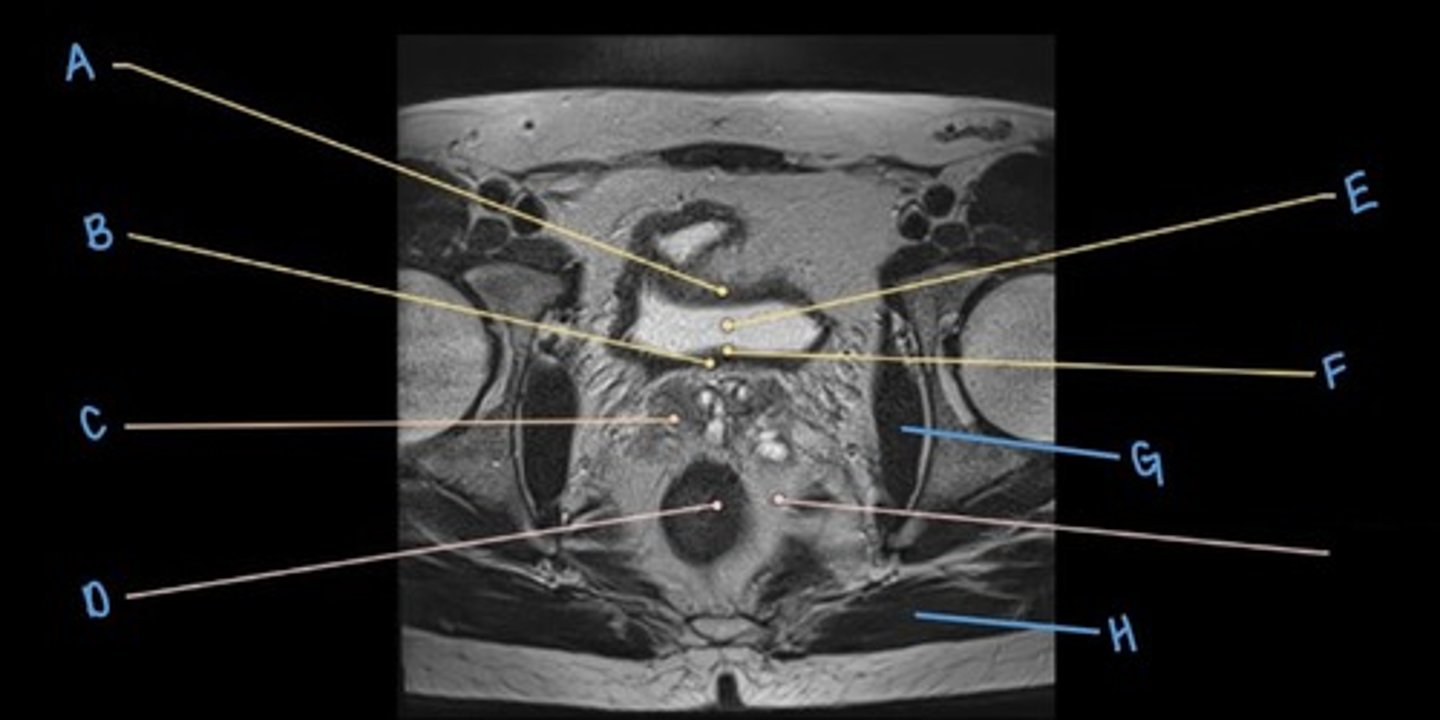

bladder

A

ureter

B & E

seminal vesicles

C

rectum

D

coccyx

F